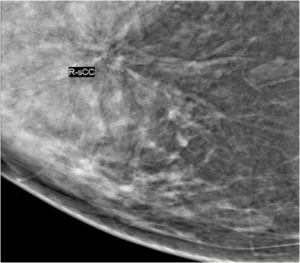

43 year female patient has come for routine screening mammogram.